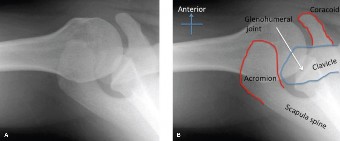

--- _Figure 2–30_A: Axillary view. B: Axillary view with annotations. Traumatic anterior instability is a common shoulder problem with an estimated incidence of 1.7%. This term encompasses both frank dislocations that require a manual reduction as well as incomplete subluxations that spontaneously reduce. It is particularly common in the young and athletic population, and it is significantly more common than other forms of instability including posterior or multidirectional instability. Understanding the natural history of anterior instability is important, as it serves as a guide to treatment. Young patients have a very high risk of recurrence; patients <20 years old have a 90% recurrence risk, between 20 and 40 years old have a 60% recurrence risk, and >40 years old have a 10% risk. Recurrent events are a predictor for arthritis and necessitate aggressive treatment, particularly in the young patient.